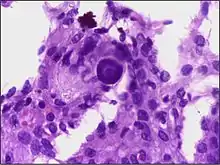

![]() | Hodgkin's lymphoma | Micrograph of a lymph node in Hodgkin's lymphoma with the characteristic Reed-Sternberg cell. RS cell is a large cell with abundant amophophilic cytoplasm and binucleate mirror image nuclei. Each nucleus contains an acidophilic nucleolus surrounded by a halo. | Category: Histopathology of Hodgkin's lymphoma | Hodgkin's lymphoma |